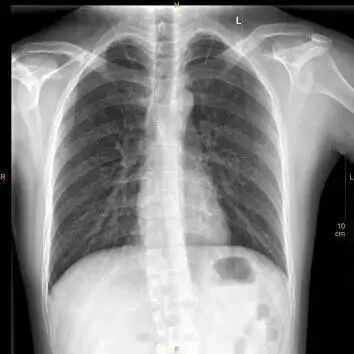

③这个文胸虽然没有钢圈,但也有很多扣子。

X光拍片为什么要等【影像科普】拍片为什么会要求脱衣服?_https://www.jmylbn.com_新闻资讯_第6张